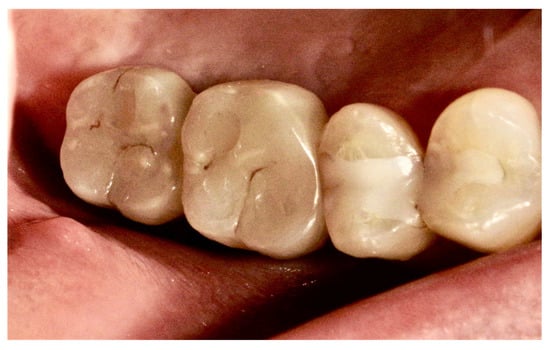

The final diagnosis of idiopathic osteosclerosis was confirmed. A six-month follow-up showed good healing, and prosthesis on dental implants was performed (Figure 8, Figure 9 and Figure 10).

Figure 8.

Good healing of soft tissues.

Juxta-gingival view of the surgical site: (a) preoperative view; (b) implants’ placement; (c) prosthetic on implants.

Figure 10.

Crowns on implants.